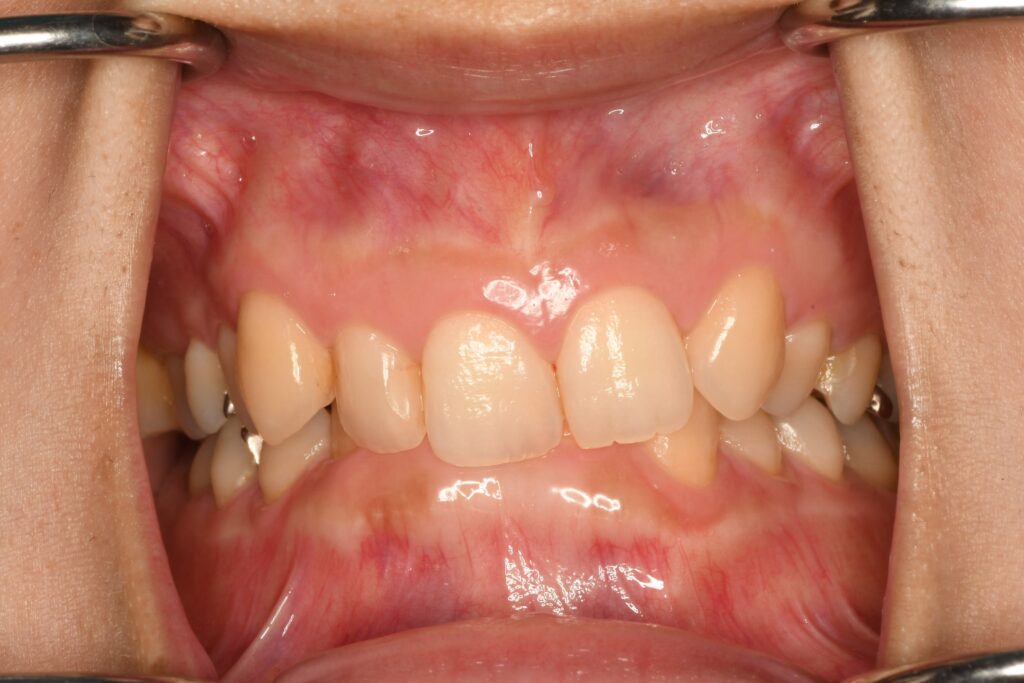

上の前歯が噛みこんでいる(過蓋咬合)のが気になる30代女性のケースです。下の前歯が完全に隠れています。理想なのは下の前歯が3分の1から半分ぐらい隠れる状態です。この様なケースに限らずですが精密検査をして状況判断をする必要があると考えています。患者さん自身が気になっている歯並びのほとんどが原因ではなく、結果がそうなっていることがほとんどです。できる限り原因の改善をしていく必要があると考えています。

検査結果から奥歯の噛み合わせも影響していると判断しました。